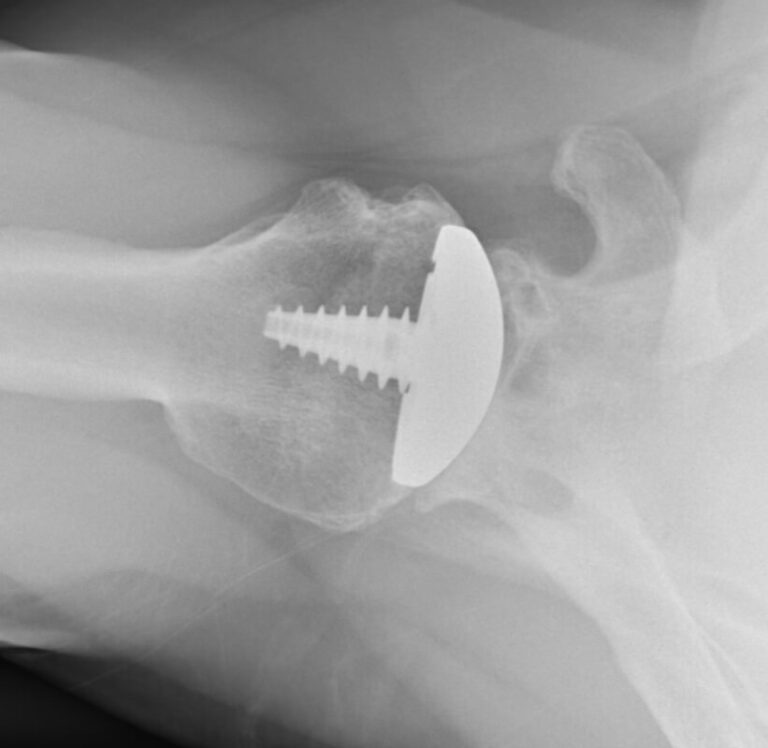

Arthrosurface, HemiCap Large